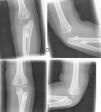

The radiographs of both elbows showed a proximal radioulnar synostosis (Figs. 1 and 2). The radiographs of the spine (Fig. 3) did not reveal any anomalies.

The patient did not report any kind of pain in the range of movement of the elbow or the wrist and was able to grasp objects and manipulate them for games and everyday activities (Fig. 4).